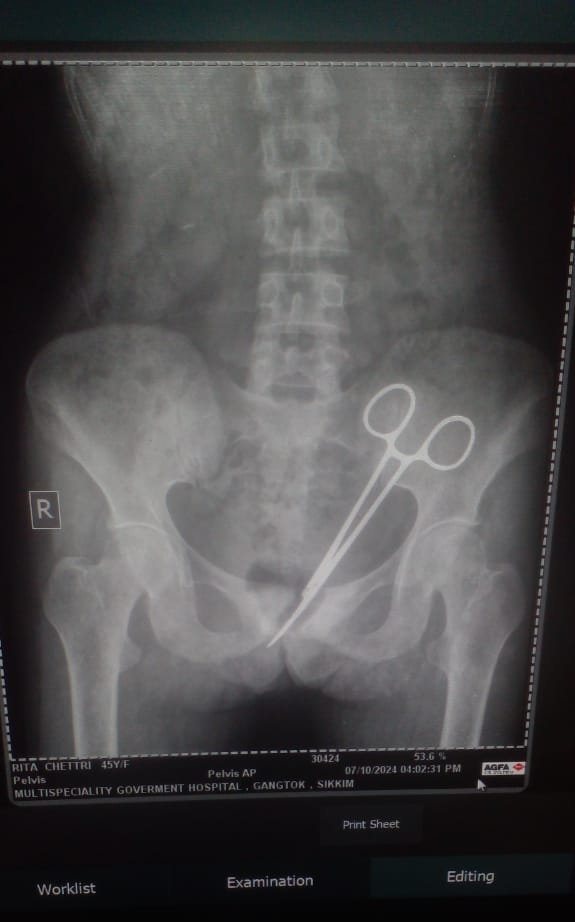

Years passed without a clear diagnosis until Rita developed urinary issues this year. A biopsy in Namchi revealed concerning results, leading to a referral back to STNM Hospital. An X-ray on October 7 revealed the astonishing presence of surgical forceps in her abdomen. The forceps were successfully removed on October 8.

Rita’s husband, Balaram Chetri, expressed his shock and disbelief, stating, “I thought it was impossible. The doctors assured us they could remove it, and they did.”